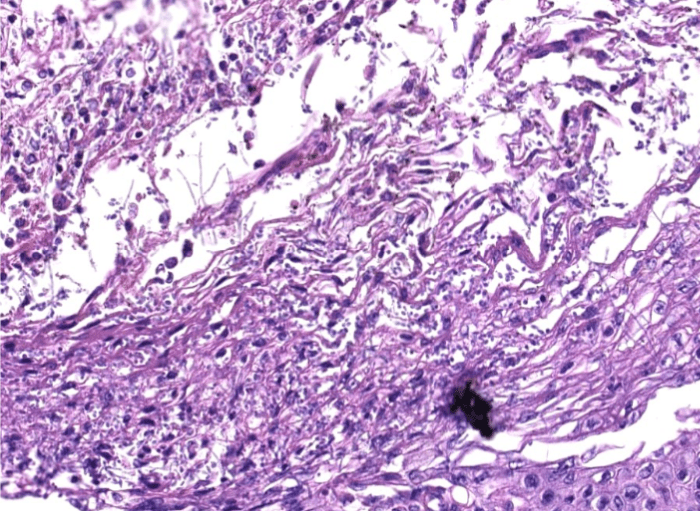

lung adenocarcinoma